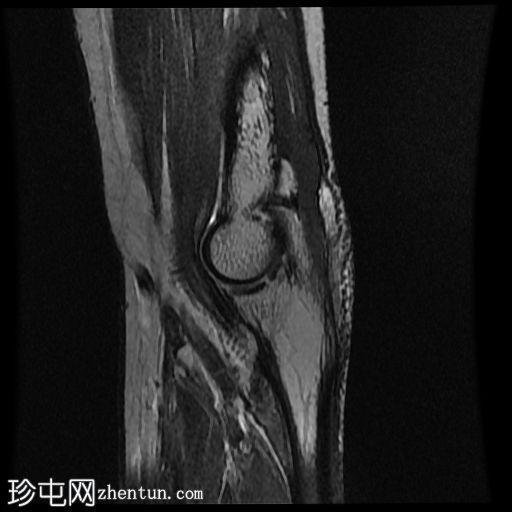

MRI

矢状位

T2加权像

鹰嘴滑囊内积液,覆盖于肱三头肌腱上方。滑囊结构复杂,囊壁增厚,内部可见细小间隔,周围可见皮下积液信号。

鹰嘴滑囊炎是患者肘关节肿胀的原因,可能由过度使用引起,因为患者无明显的急性外伤史。